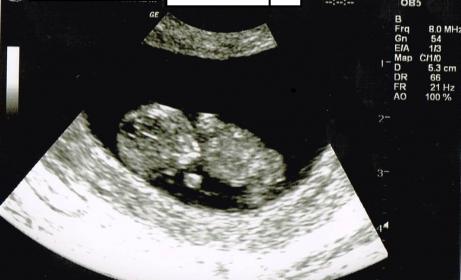

Baby is upside down, so can't guess :( It's a cutie :)

I know that it's upside down but still the bottom picture screams girl to me! Do you see what I'm saying?

I'm sorry but I can't guess either way. It's a bummer when the baby is upside down. My baby was the same a week and a half ago. Best of luck that you get what you wish for x

bumping this.....The second one down looks girly? RIght????

Honestly, no...it doesn't really look girlie to me. I don't think you can tell anything at all by any of those pictures. For that age, you need a nub shot and you don't have one. Sorry.